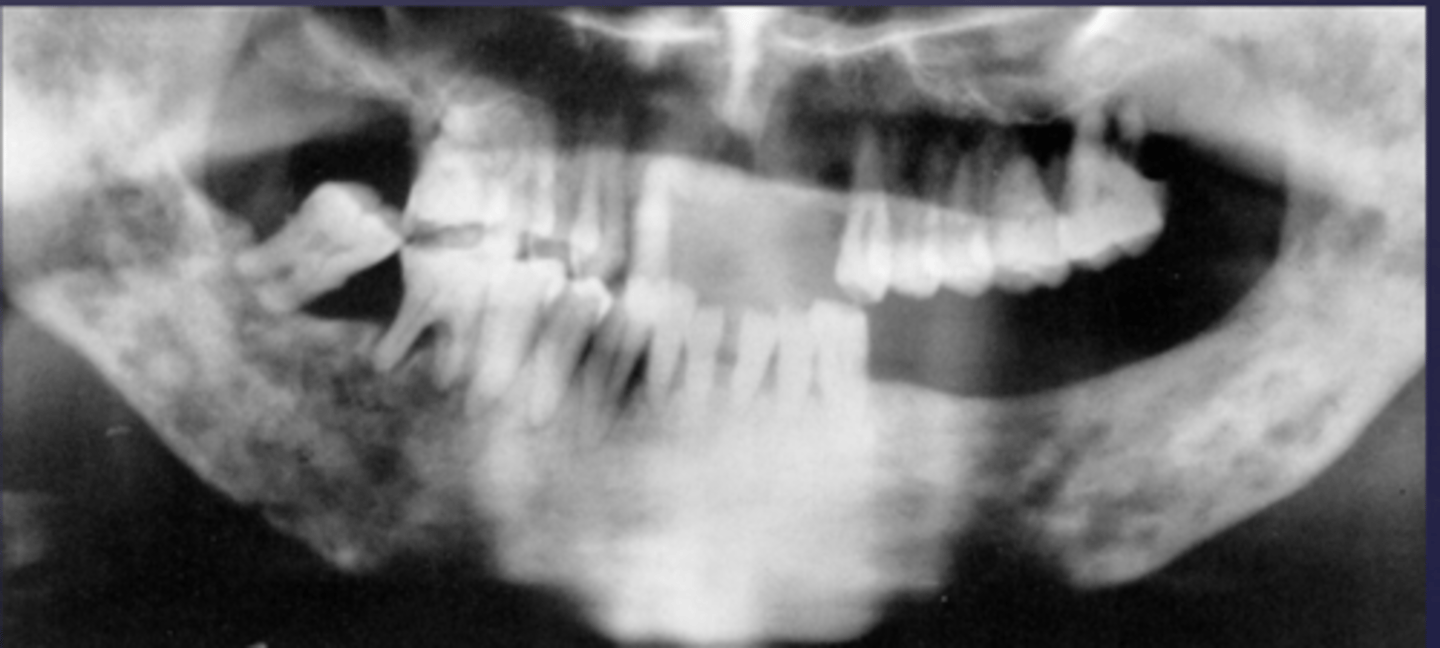

How would you describe the lesion?

- Ill-defined, moth eaten area in the posterior mandible

- How would you describe the lesion?

What category would you put this lesion into?

malignant

all of the following could be a differential diagnosis for this lesion except?

A. squamous cell carcinoma

B. multiple myeloma

C. osteogenic sarcoma

- Ill-defined moth eaten area in the posterior mandible

- Radiopacities extending beyond the mandibular borders.

What would be a differential diagnosis for this lesion?

- Osteogenic sarcoma

- Squamous cell CA